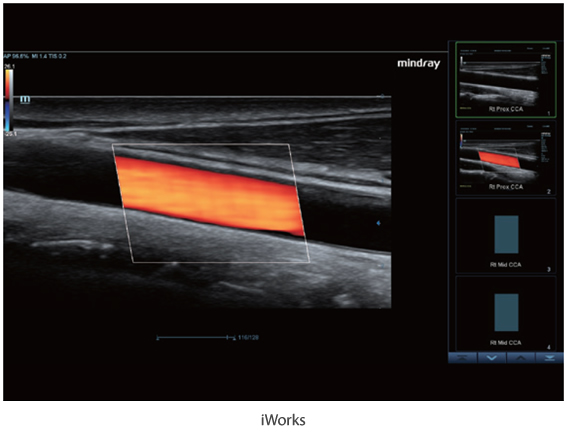

Многофункциональная система DC-60 Exp с X-Insight представляет собой комплексное решение, которое помогает управлять повседневной клинической практикой с легкостью и уверенностью.

Основываясь на глубоком понимании потребностей клиентов, компания Mindray разработала систему DC-60 Exp с X-Insight, чтобы обеспечить высокую производительность и точность визуализации вкупе с наглядностью, исключительной интеллектуальностью и огромным опытом.